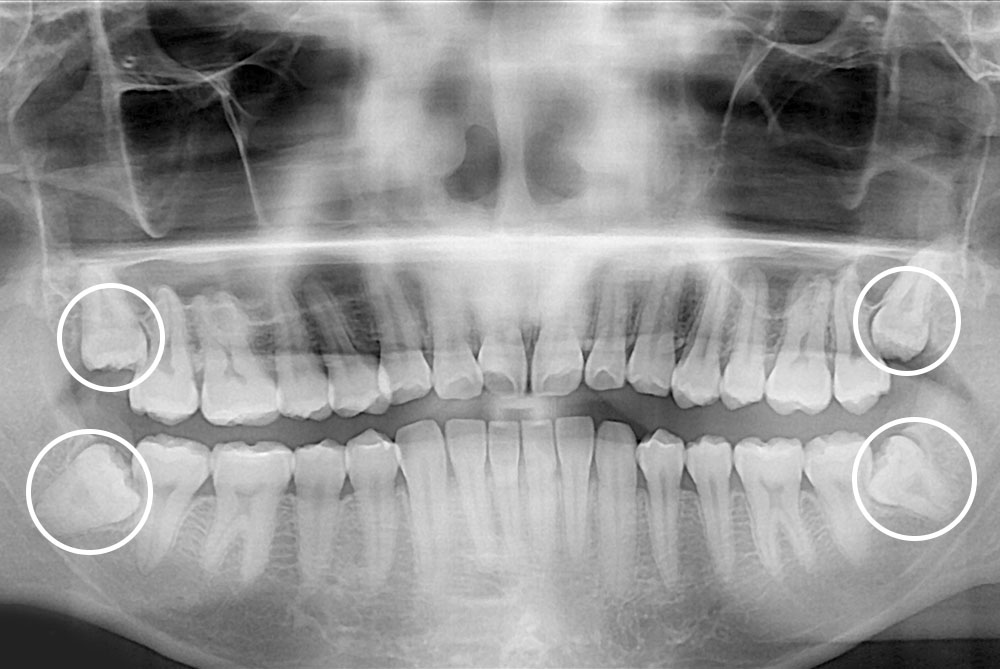

[사랑니] 매복 사랑니 발치

치료후 : 2020-07-23

세종치과는 구강악안면외과학 박사이신 원장님이 발치하는 치과입니다.